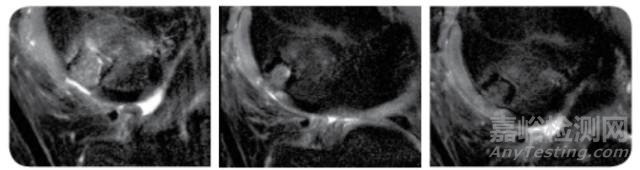

第二例:男,49歲

術(shù)后3周 術(shù)后6周 術(shù)后12周